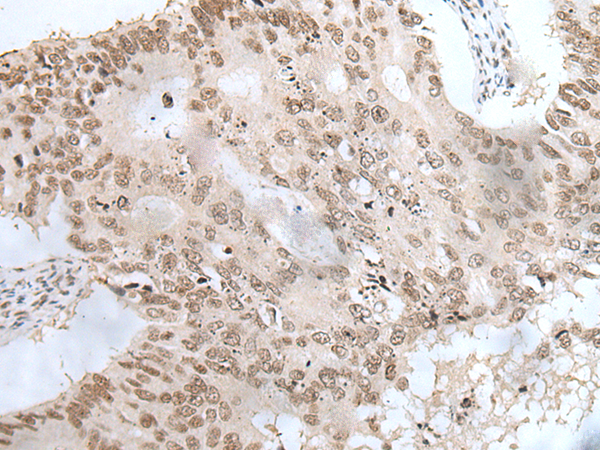

ELISA, IHC

IHC positive control:

Human colorectal cancer and human ovarian cancer

IHC Recommend dilution:

20-100